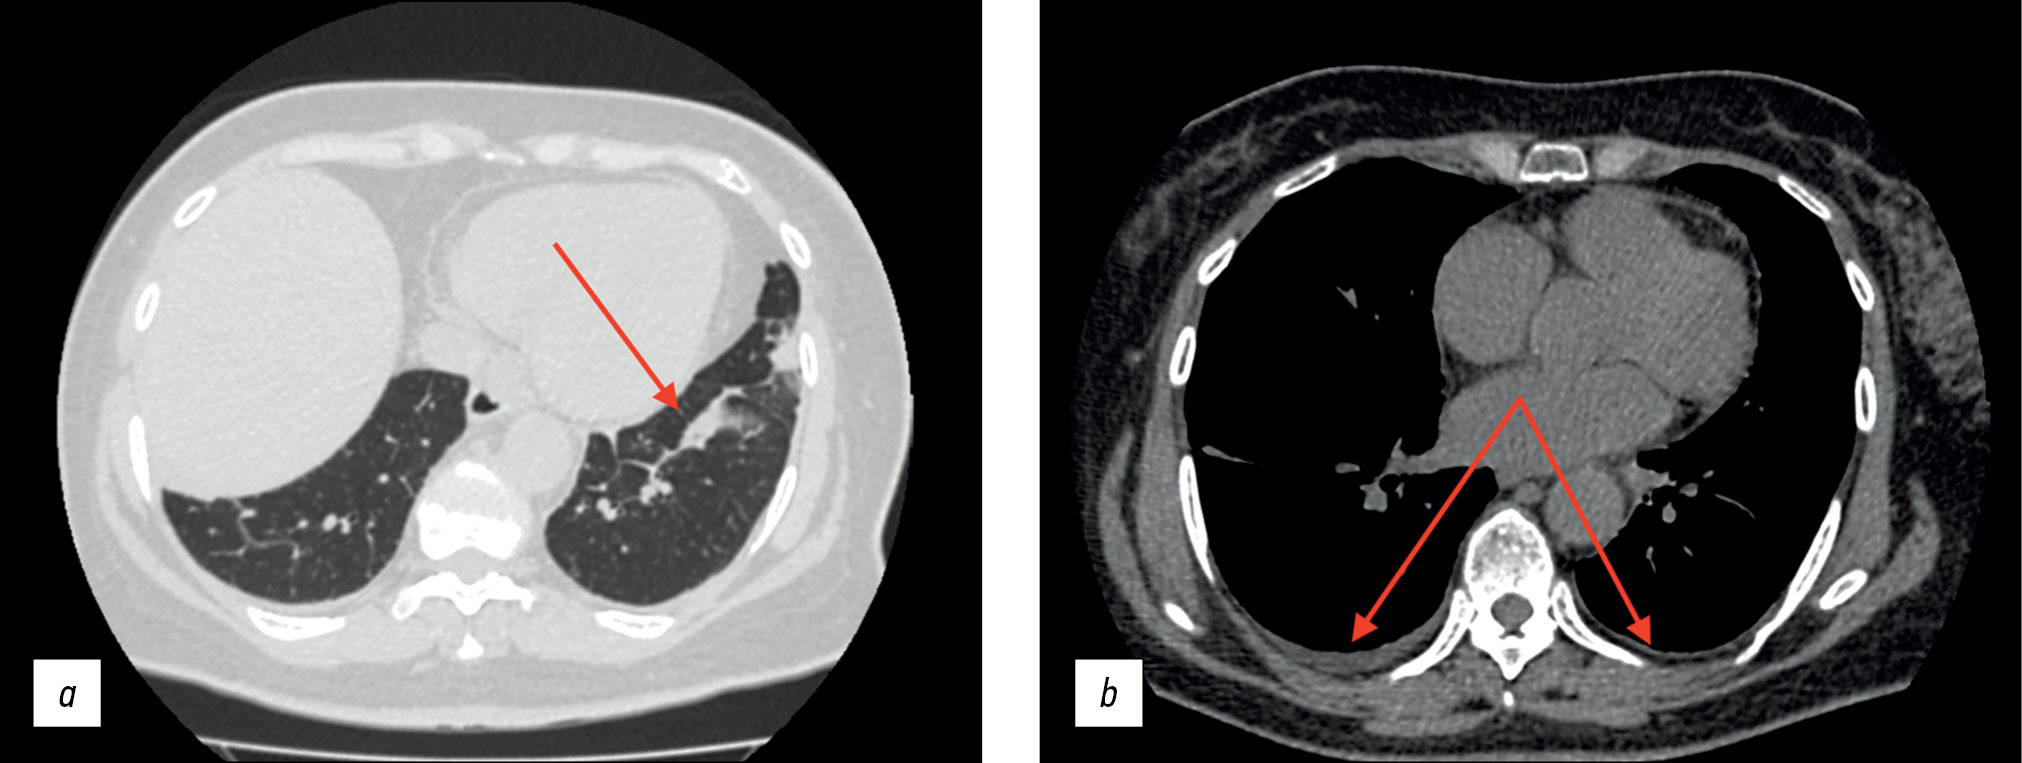

The patient was generally well in August 2020, but she began experiencing daily elevations in body temperature to 38.5°C–39°C, followed by muscular and joint pain. Antipyretics had no effect; therefore, the patient was admitted to the Infection Department inpatient unit and received antibiotics and oral and intravenous detoxification medications. The medication improved the overall condition, although the subfebrile body temperature continued in the evenings. The thoracic CT scan revealed modest effusion in the pleural cavities, bilateral bands of peribronchovascular thickening, small subsegmental compression atelectasis in the basal regions of both lungs, and elevated hemidiaphragm (Figure 1).

Fig. 1. Thoracic computed tomography scan (August 2020); axial plane: the red arrows show (a) subsegmental compression atelectasis and (b) mild pleural effusion.